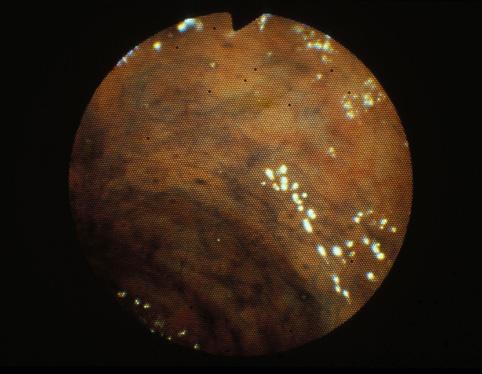

疾病(病理主体)的分类炎症性・溃疡性疾患/阿米巴痢疾

部位(按器官分)大肠/直肠

检查方法内窥镜